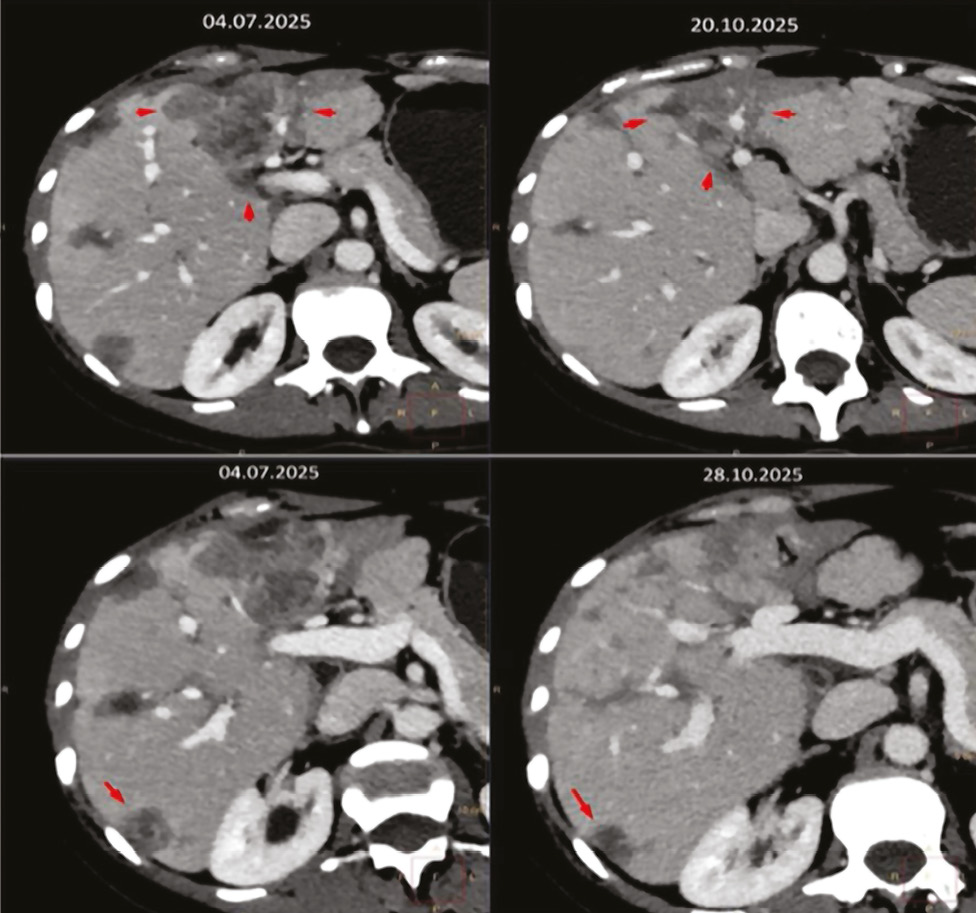

Жовтень 2025 р. КТ ОГП та ОЧП, заочеревинного простору та ОМТ з контрастом. Висновок: стан у процесі терапії через Са правої грудної залози. Порівняно з КТ від 07.2025 р. фіксується зменшення таргетних вогнищ печінки на 19%, що може вкладатися в стабілізацію процесу (рис. 2). Нарешті КТ-картина без істотних змін, зокрема вузлики в легенях, потовщення інтерстиціального компонента, вторинне ураження кісток — стабілізація процесу.

Рис. 2. Динаміка КТ ОГК та ОЧП, заочеревинного простору та ОМТ з контрастом

Після призначення трастузумабу деркстекану у пацієнтки відмічалося поступове зниження рівня онкомаркерів і стабілізація метастазів. На КТ виявлено зменшення кількості та розміру печінкових метастазів на 19%, стабілізацію ураження кісток та легень. Проліферативні маркери: ER 80%, Pr 95%, HER2/Neu +1, Ki-67 10%.